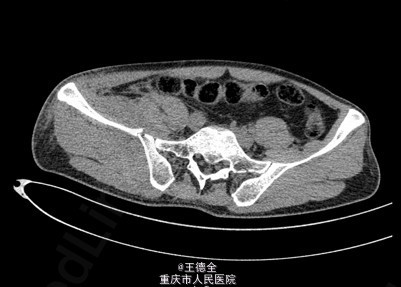

患者男性,51岁,因“高坠伤致左腰部及右髋部疼痛伴活动障碍3天”入院。

查体:急性痛苦面容,神志清楚,平车送入病房,右髋部软组织稍肿胀,局部皮肤完整,未见明显皮疹,挫擦伤及出血点.右股骨髁上骨牵引在位,左腰椎伴明显压痛,骨盆挤压实验阳性,可扪及骨擦音,骨擦感.双下肢感觉,活动,血循良好,足背动脉搏动好;右踝关节主动活动受限,被动活动正常。右侧各足趾背伸、跖屈活动正常,其余各关节活动正常。骨盆X线片示:右侧髂骨、髋臼、双侧耻骨上支、右侧耻骨下支多发骨折,左侧髂骨翼骨折,骨盆出入口右侧份形态失常。辅查影像学资料见下图。

初步诊断:右髋臼粉碎性骨折(Judet X 型) ,诊疗计划:完善双下肢静脉彩超等检查;给予预防深静脉血栓、骨牵引治疗;给予止痛等对症支持治疗;密切观察病情变化,根据病情及时处理。